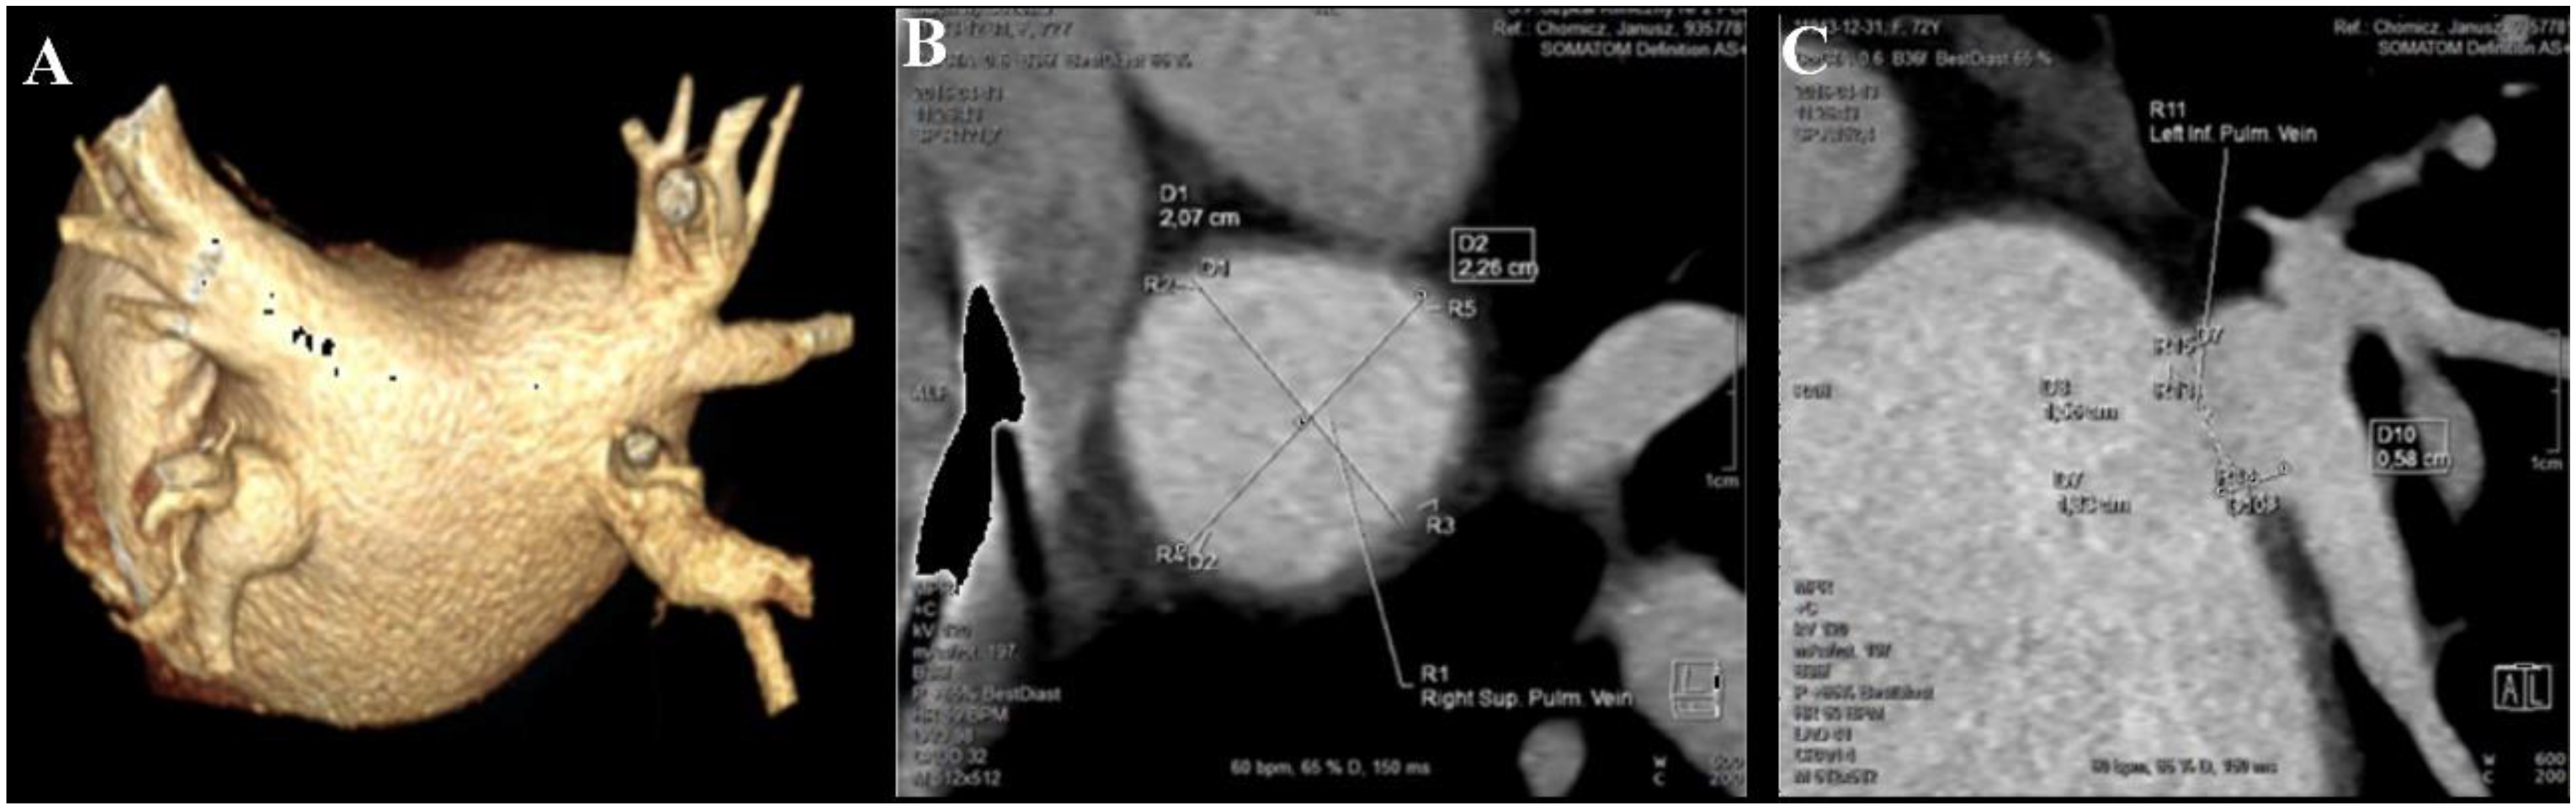

2.2. Pulmonary Veins Measurement